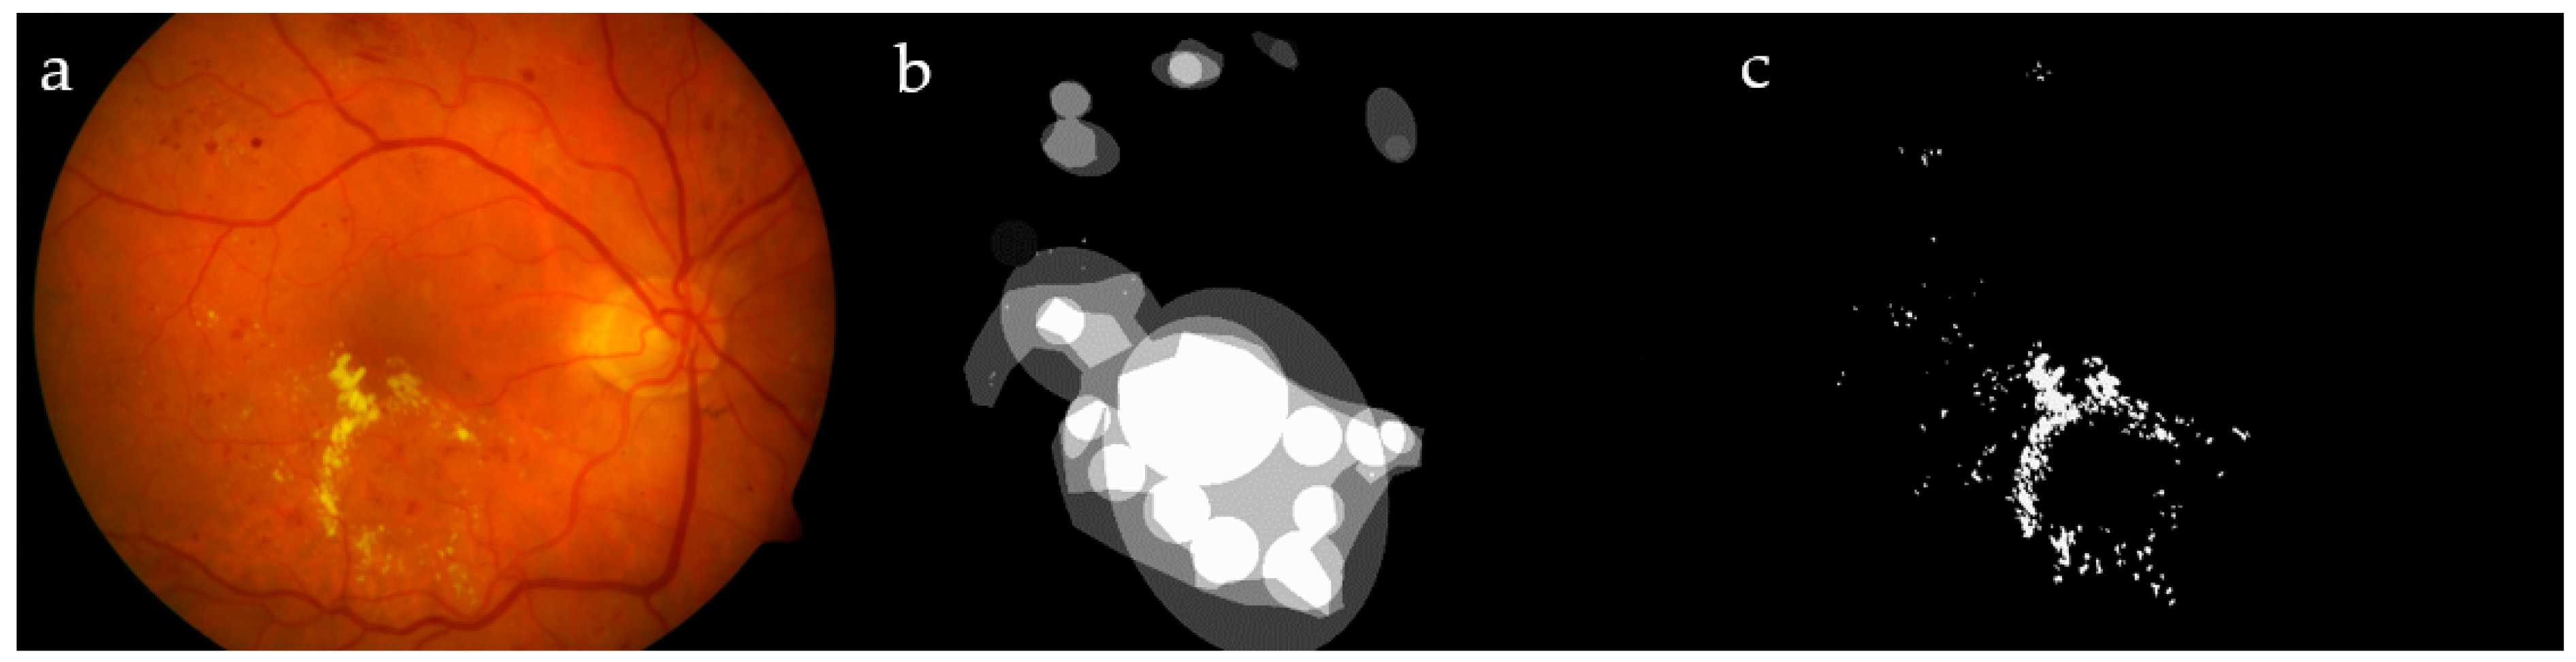

Ocular diseases have sparked remarkable interest because they are serious and influence a large portion of the population. An example of a relevant ocular disease is diabetic retinopathy (DR) [1], because it may cause blindness in working-age patients. DR is a progressive pathology that can change from mild to severe non-proliferative disease, and it is an important factor contributing to blindness. This disease affects up to 80% of those who have suffered from diabetes for 10 years or more [2]. Due to increases in life expectancy and other factors, the number of people affected by exudates is growing [3]. Exudates are one of the main symptoms of DR, caused by the leakage of proteins and lipids from damaged blood vessels in the retina. They can be recognized as yellow lesions distributed on the interior surface of the eye, with different sizes in different locations, according to the severity of the retinopathy (Figure 1a). From a practical point of view, it must be noted that DR does not show salient symptoms in the early stages [4]; therefore, it is a challenge to identify the disease early enough to give a better chance for successful treatment [5]. To diagnose and implement a treatment, screening checks are required that, at present, require professional clinicians. On the other hand, automated mass screening tasks are an active area of research with promising potential in the field of computer vision [3]. Other examples of artifacts that may appear in the retina include hemorrhage, the escape of blood from vessels that appears as red lesions, and different types of pus [2]. The World Diabetes Foundation estimates that more than 640 million people will suffer from diabetes by the year 2040 [6].

Figure 1. Image #19 from DIARETDB1 (a); ground truths from the dataset (b) and by our ophthalmologist (c), for a visual comparison.

The ground truth in DIARETDB0 was defined precisely in each image, including both the center coordinates and the type of each pus as an exudate/hemorrhage/cotton–wool area, while, in DIARETDB1, the ground truth was prepared by four experts, showing the affected regions and not specifying the infected areas. A set of random images from these datasets containing hard exudates was segmented manually by our expert ophthalmologist; the set included 19 DIARETDB0 and another 10 DIARETDB1 images affected by DR. Figure 1 shows a sample image from DIARETDB1, together with its ground truth provided in the dataset and created by our ophthalmologist.

The ground truths introduced in the two datasets are not suitable for our methodology. The former reports only the center of the exudate, while the latter indicates the affected region in a rough way. A comparison was made between our expert and the DIARETDB1 ground truth (GT), showing 95.7% sensitivity and 90.8% specificity.